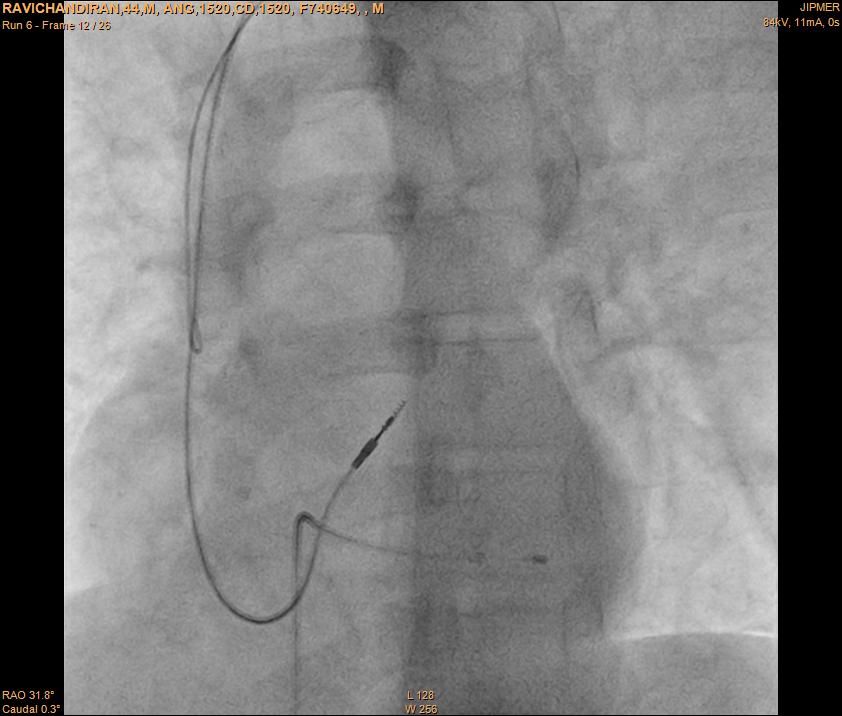

rvot_lead.jpg

RVOT pacing

rvot_pacing_ecg.jpg